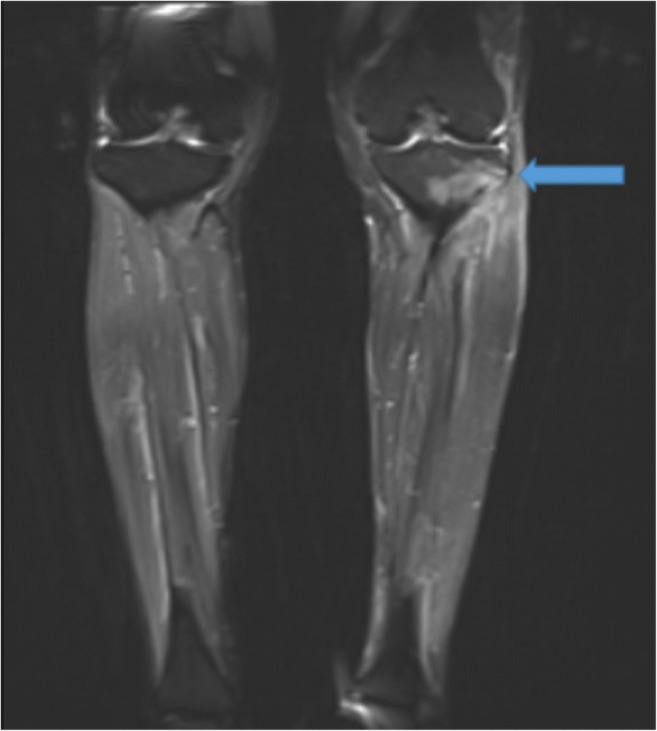

While history and physical examination are usually sufficient for diagnosis, imaging may be useful in cases of unclear and vague presentations of MTSS. Magnetic resonance imaging (MRI) demonstrates superior sensitivity and specificity in early tibial stress injuries [2, 31]. T2-weighted images reveal cortical thickening with periosteal reaction and reactive marrow edema at the site of maximal pain (Fig. 4a, b). Bone scans show a distinct appearance with uptake along the posteromedial tibia on delayed-phase images. Uptake is longitudinally oriented with greater than one third tibial involvement, as opposed to localized uptake in stress fractures [5].

Fig. 4.

Axial (a) and coronal (b) T2-weighted fat-suppressed magnetic resonance imaging scans demonstrate medial tibial stress syndrome (shin splints). Cortical thickening with periosteal reaction and reactive marrow edema along the anterior medial aspect of the proximal to mid-tibial diaphysis, at the site of maximum perceived patient pain is observed (arrows). No acute stress fracture is noted.